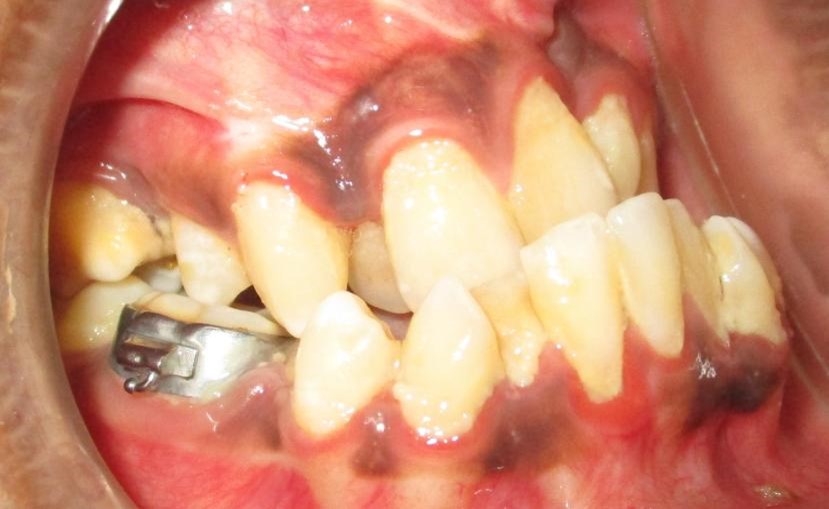

Protruding lower jaw with small upper jaw leading to facial imbalance

Crowding of the teeth and malocclusion of the same patient